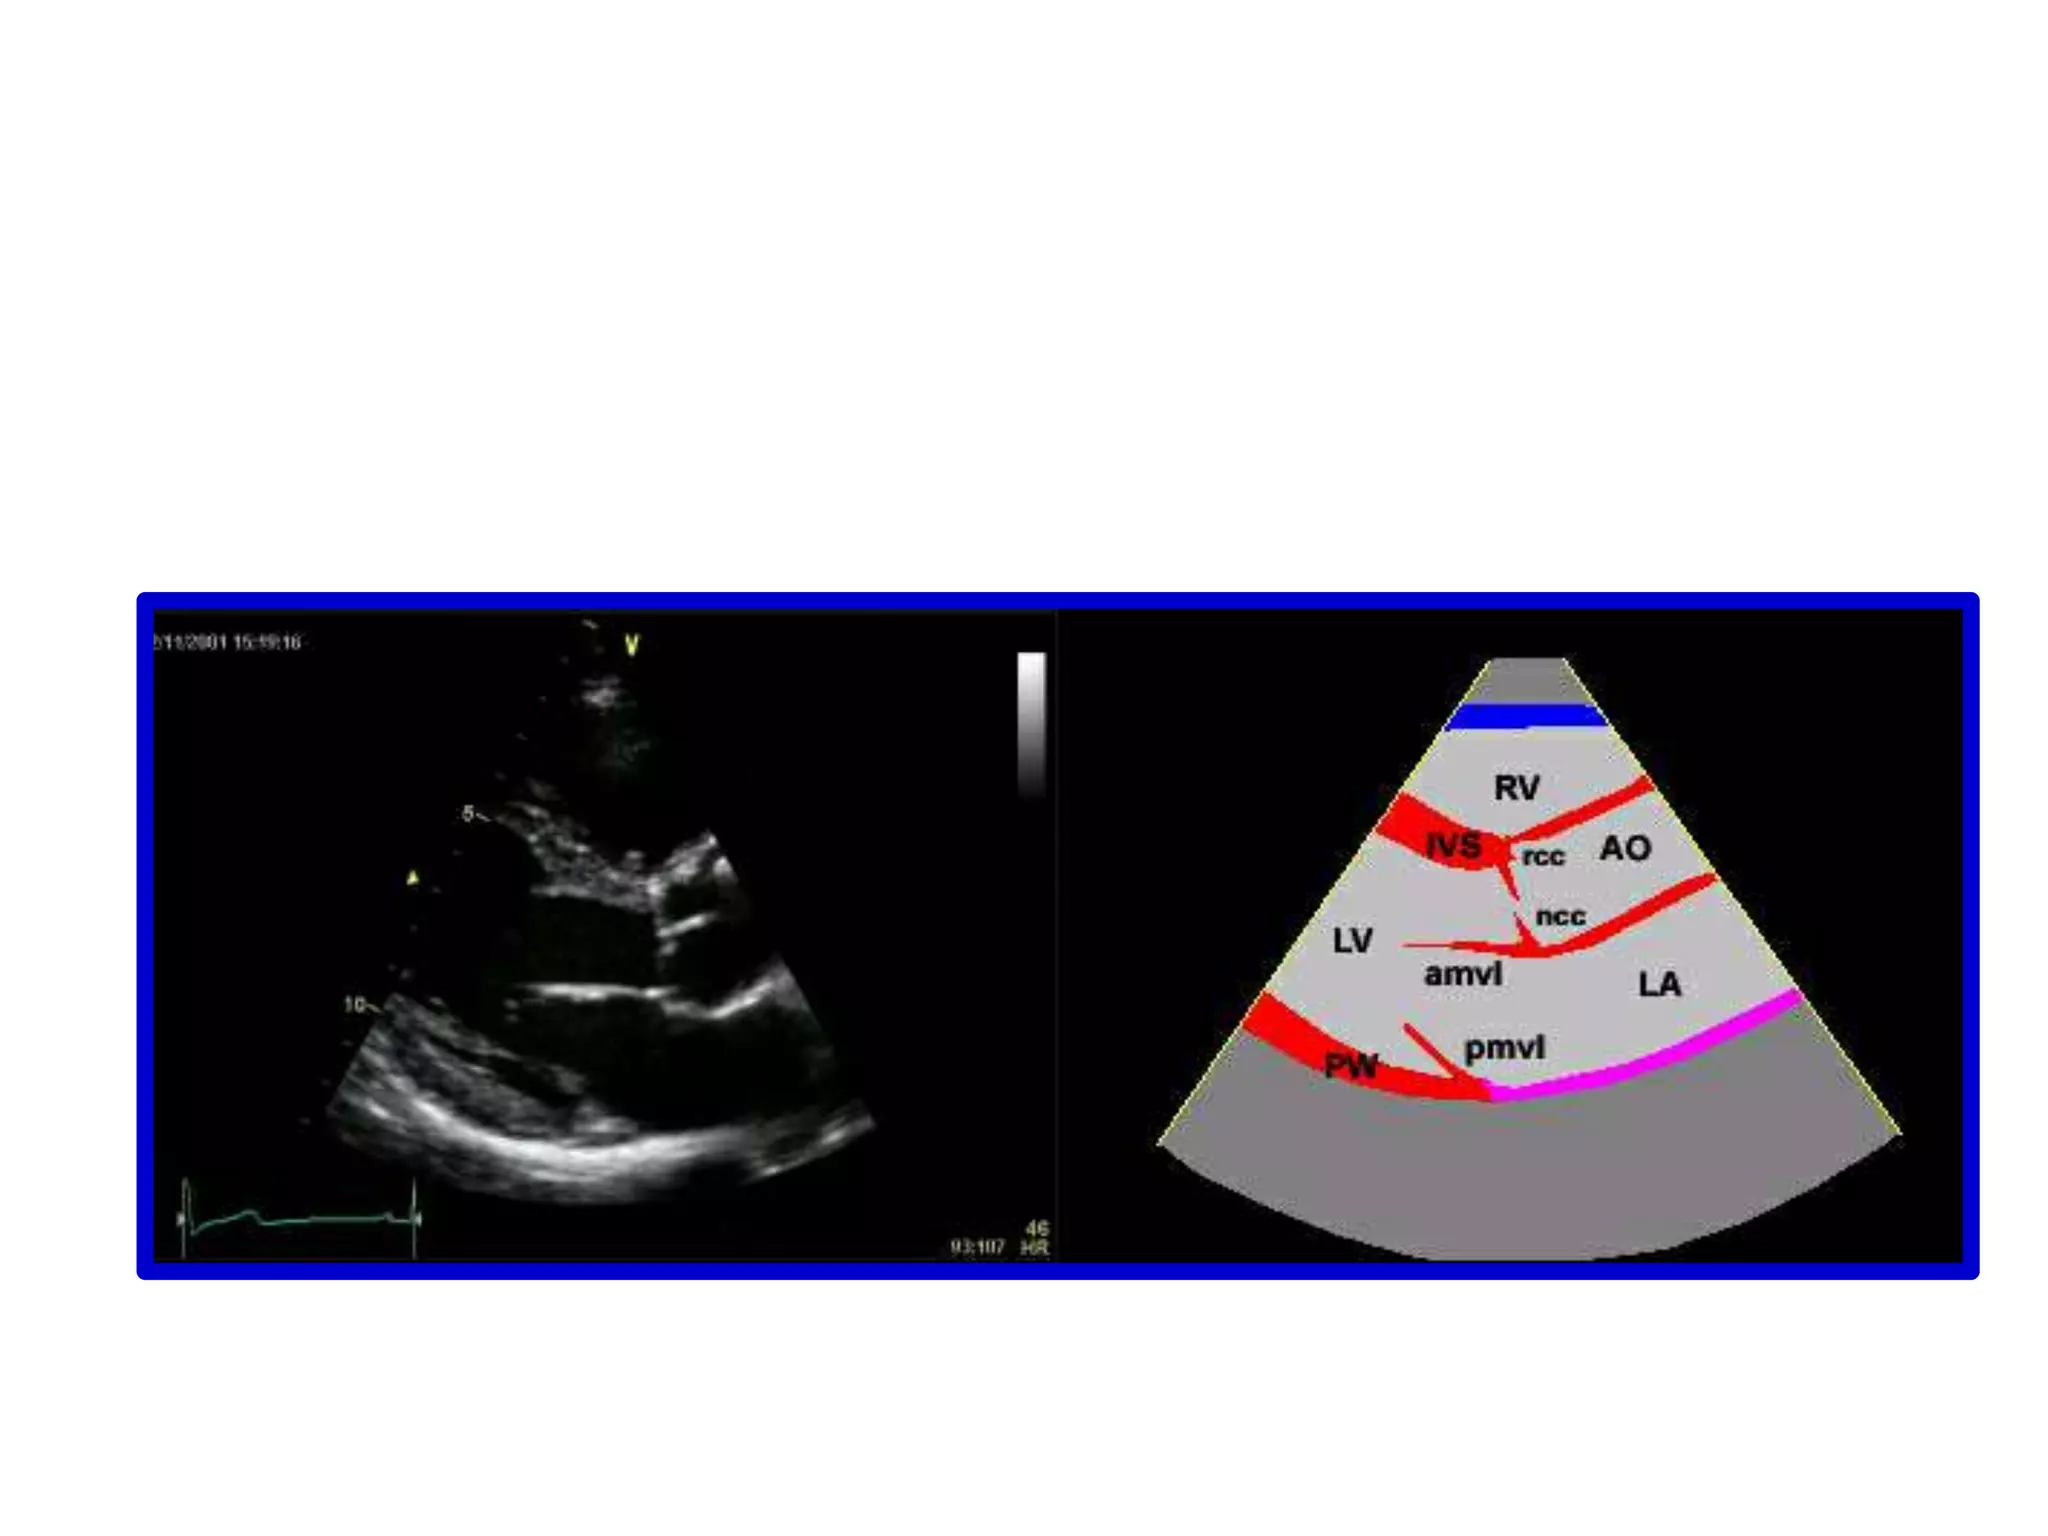

Sweeping begins at the base of the heart which appears on the rt of the screenThe left atrium, the mitral valve and the right ventricular outflow tract are seen.

Sweeping begins atthe base of the heart which appears on the rt of the screenThe left atrium, the mitral valve and the right ventricular outflow tract are seen.